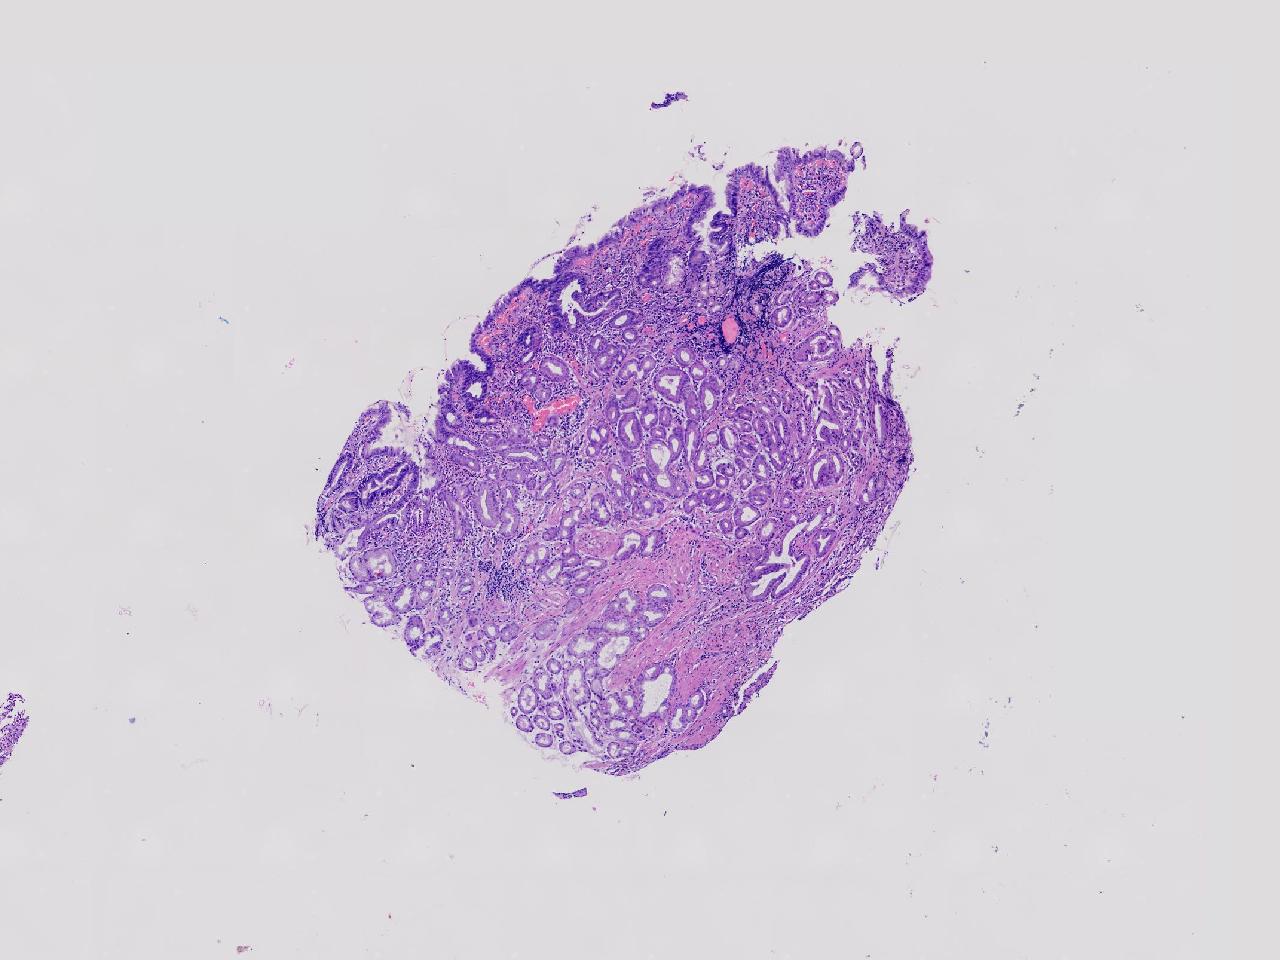

炎? 低瘤变?

胃体上部见一大小约2厘米的溃疡灶,表覆白苔,周边充血,水肿明显,活检3块。

胃体活检

灰白色不整形软组织3块,直径均0.2厘米。

深在性囊性胃炎,少量溃疡组织

深在性囊性胃炎伴溃疡